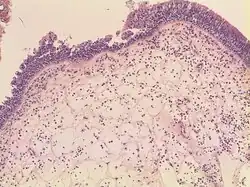

Polipy nosa – powstają w wyniku zmian zapalnych lub alergicznych błony śluzowej nosa. Najczęściej wychodzą ze środkowego przewodu nosowego, zatok szczękowych lub sitowych. Tworzenie polipa rozpoczyna się od obrzęku błony śluzowej, rozrostu tkanki podśluzowej, gromadzenia się płynu i tworzeniem się szypuły poprzez grawitacyjne opadanie naciągniętego zdwojenia błony śluzowej wypełnionego płynem.